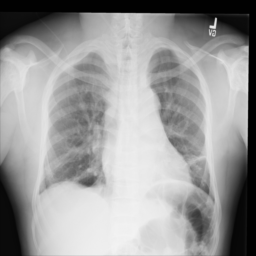

Anomaly detection is the problem of recognizing abnormal inputs based on the seen examples of normal data. Despite recent advances of deep learning in recognizing image anomalies, these methods still prove incapable of handling complex medical images, such as barely visible abnormalities in chest X-rays and metastases in lymph nodes. To address this problem, we introduce a new powerful method of image anomaly detection. It relies on the classical autoencoder approach with a re-designed training pipeline to handle high-resolution, complex images and a robust way of computing an image abnormality score. We revisit the very problem statement of fully unsupervised anomaly detection, where no abnormal examples at all are provided during the model setup. We propose to relax this unrealistic assumption by using a very small number of anomalies of confined variability merely to initiate the search of hyperparameters of the model. We evaluate our solution on natural image datasets with a known benchmark, as well as on two medical datasets containing radiology and digital pathology images. The proposed approach suggests a new strong baseline for image anomaly detection and outperforms state-of-the-art approaches in complex medical image analysis tasks.